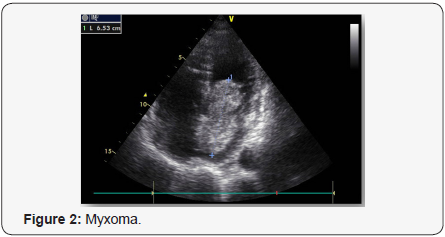

A 79-year-old woman was admitted to our hospital because of a syncopal episode followed by altered mental status. The patient was at her usual state of health with a six-month history of exertional dyspnea managed as bronchial asthma, when she suddenly lost consciousness and vomited while walking. She was transferred by ambulance to the emergency department within 40 minutes after the onset of symptoms. On arrival, she said she did not have chest pain or headache, but she was unable to provide other history. On examination, she was lethargic, with periods of unresponsiveness. There was no sign of head trauma; the remainder of the examination was normal. A radiograph of the chest showed pulmonary vascular prominence with no evidence of edema, infiltrate or effusion. An electrocardiogram revealed sinus tachycardia with ST – segment elevation in V3 through V6. Tests for creatinine kinase and troponin T were negative. Transthoracic echocardiography showed hypokinesis of the anterior, septal, and apical walls of the left ventricle. Overall left ventricle systolic function was at the lower limit of the normal range. The left atrium was dilated. There was a large pedunculated mobile echodensity in the left atrium that was attached to the atrial septum (Figures 1 & 2).The mass was obstructing flow with a mean trans mitral gradient of 17mm Hg, with a reduced stroke volume and moderate to severe pulmonary hypertension with an estimated right ventricular systolic pressure of 90 mm Hg. Subsequent transesophageal views revealed a mass 7cm x 3cm x 3.4cm with its base attached to the interatrial septum. The mass was highly mobile with multiple frondlike elements. Color Doppler imaging showed no evidence of a patent foramen ovale. Magnetic resonance imaging (MRI) of the brain revealed no new infarcts. An emergency Interventional angiography performed prior surgical excision and approximately 12 hours after the onset of symptoms revealed an occlusive filling defect in the proximal portion of the circumflexus coronary artery. Balloon dilatation and DES implantation improved filling. The patient was intubated, a nasogastric tube was placed and moved to the operating room. Subsequently, surgical resection of the left atrial mass was performed via transatrial surgical approach and the atrial septum defect repaired with a homologue patch. The resected mass was 7cm x 3cm x 3.4cm, with an irregular frondlike surface (Figures 3 & 4). On microscopical examination, the mass also had the morphologic features of a cardiac myxoma.

Echocardiography was reported to be the definitive diagnostic modality. The sensitivity of transthoracic echocardiography is about 95% determine accurately the location, the size, the attachment and the mobility of the mass. Transesophageal echocardiography has nearly 100% sensitivity for cardiac myxoma. The tumor tissue manifests as spherical – pedunculated mass attached to the endocardial surface with hypoechoic areas [25].